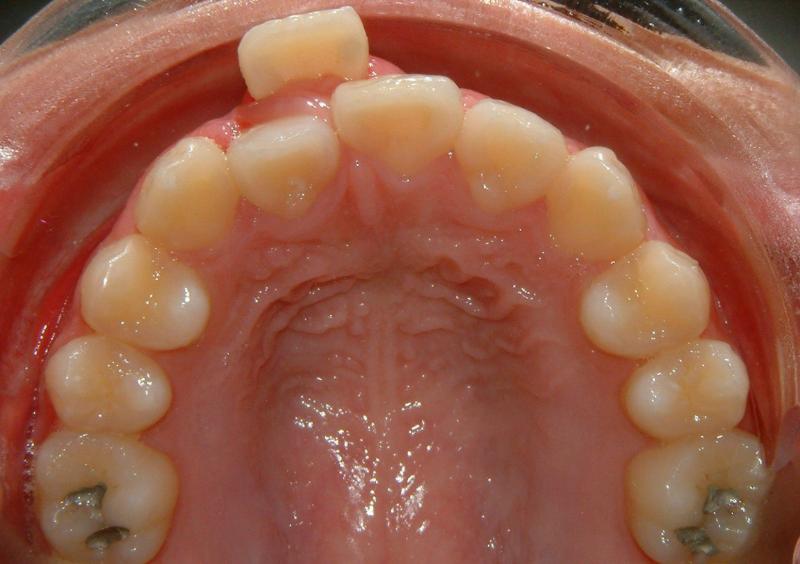

The upper right central incisor and lateral incisor form 2 rows. It would be a fatal mistake to extract either one of these two. It might be the case if the patient has no access to the correct orthodontic treatment. In this case, the 1st premolars are removed. Initial and some progress data are presented in Figs. 1-5.

Fig. 2 Upper right central and lateral incisors, forming double rows -- occlusal view